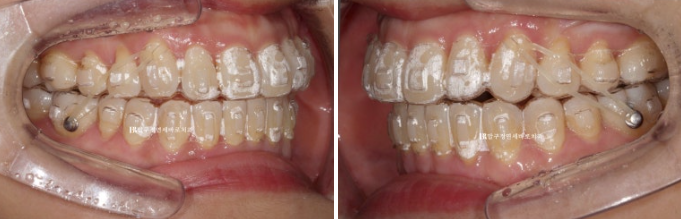

23.11

두번째 세트에서는 어금니 교합관계를 맞추기 위해서 고무줄 처방도 들어갑니다